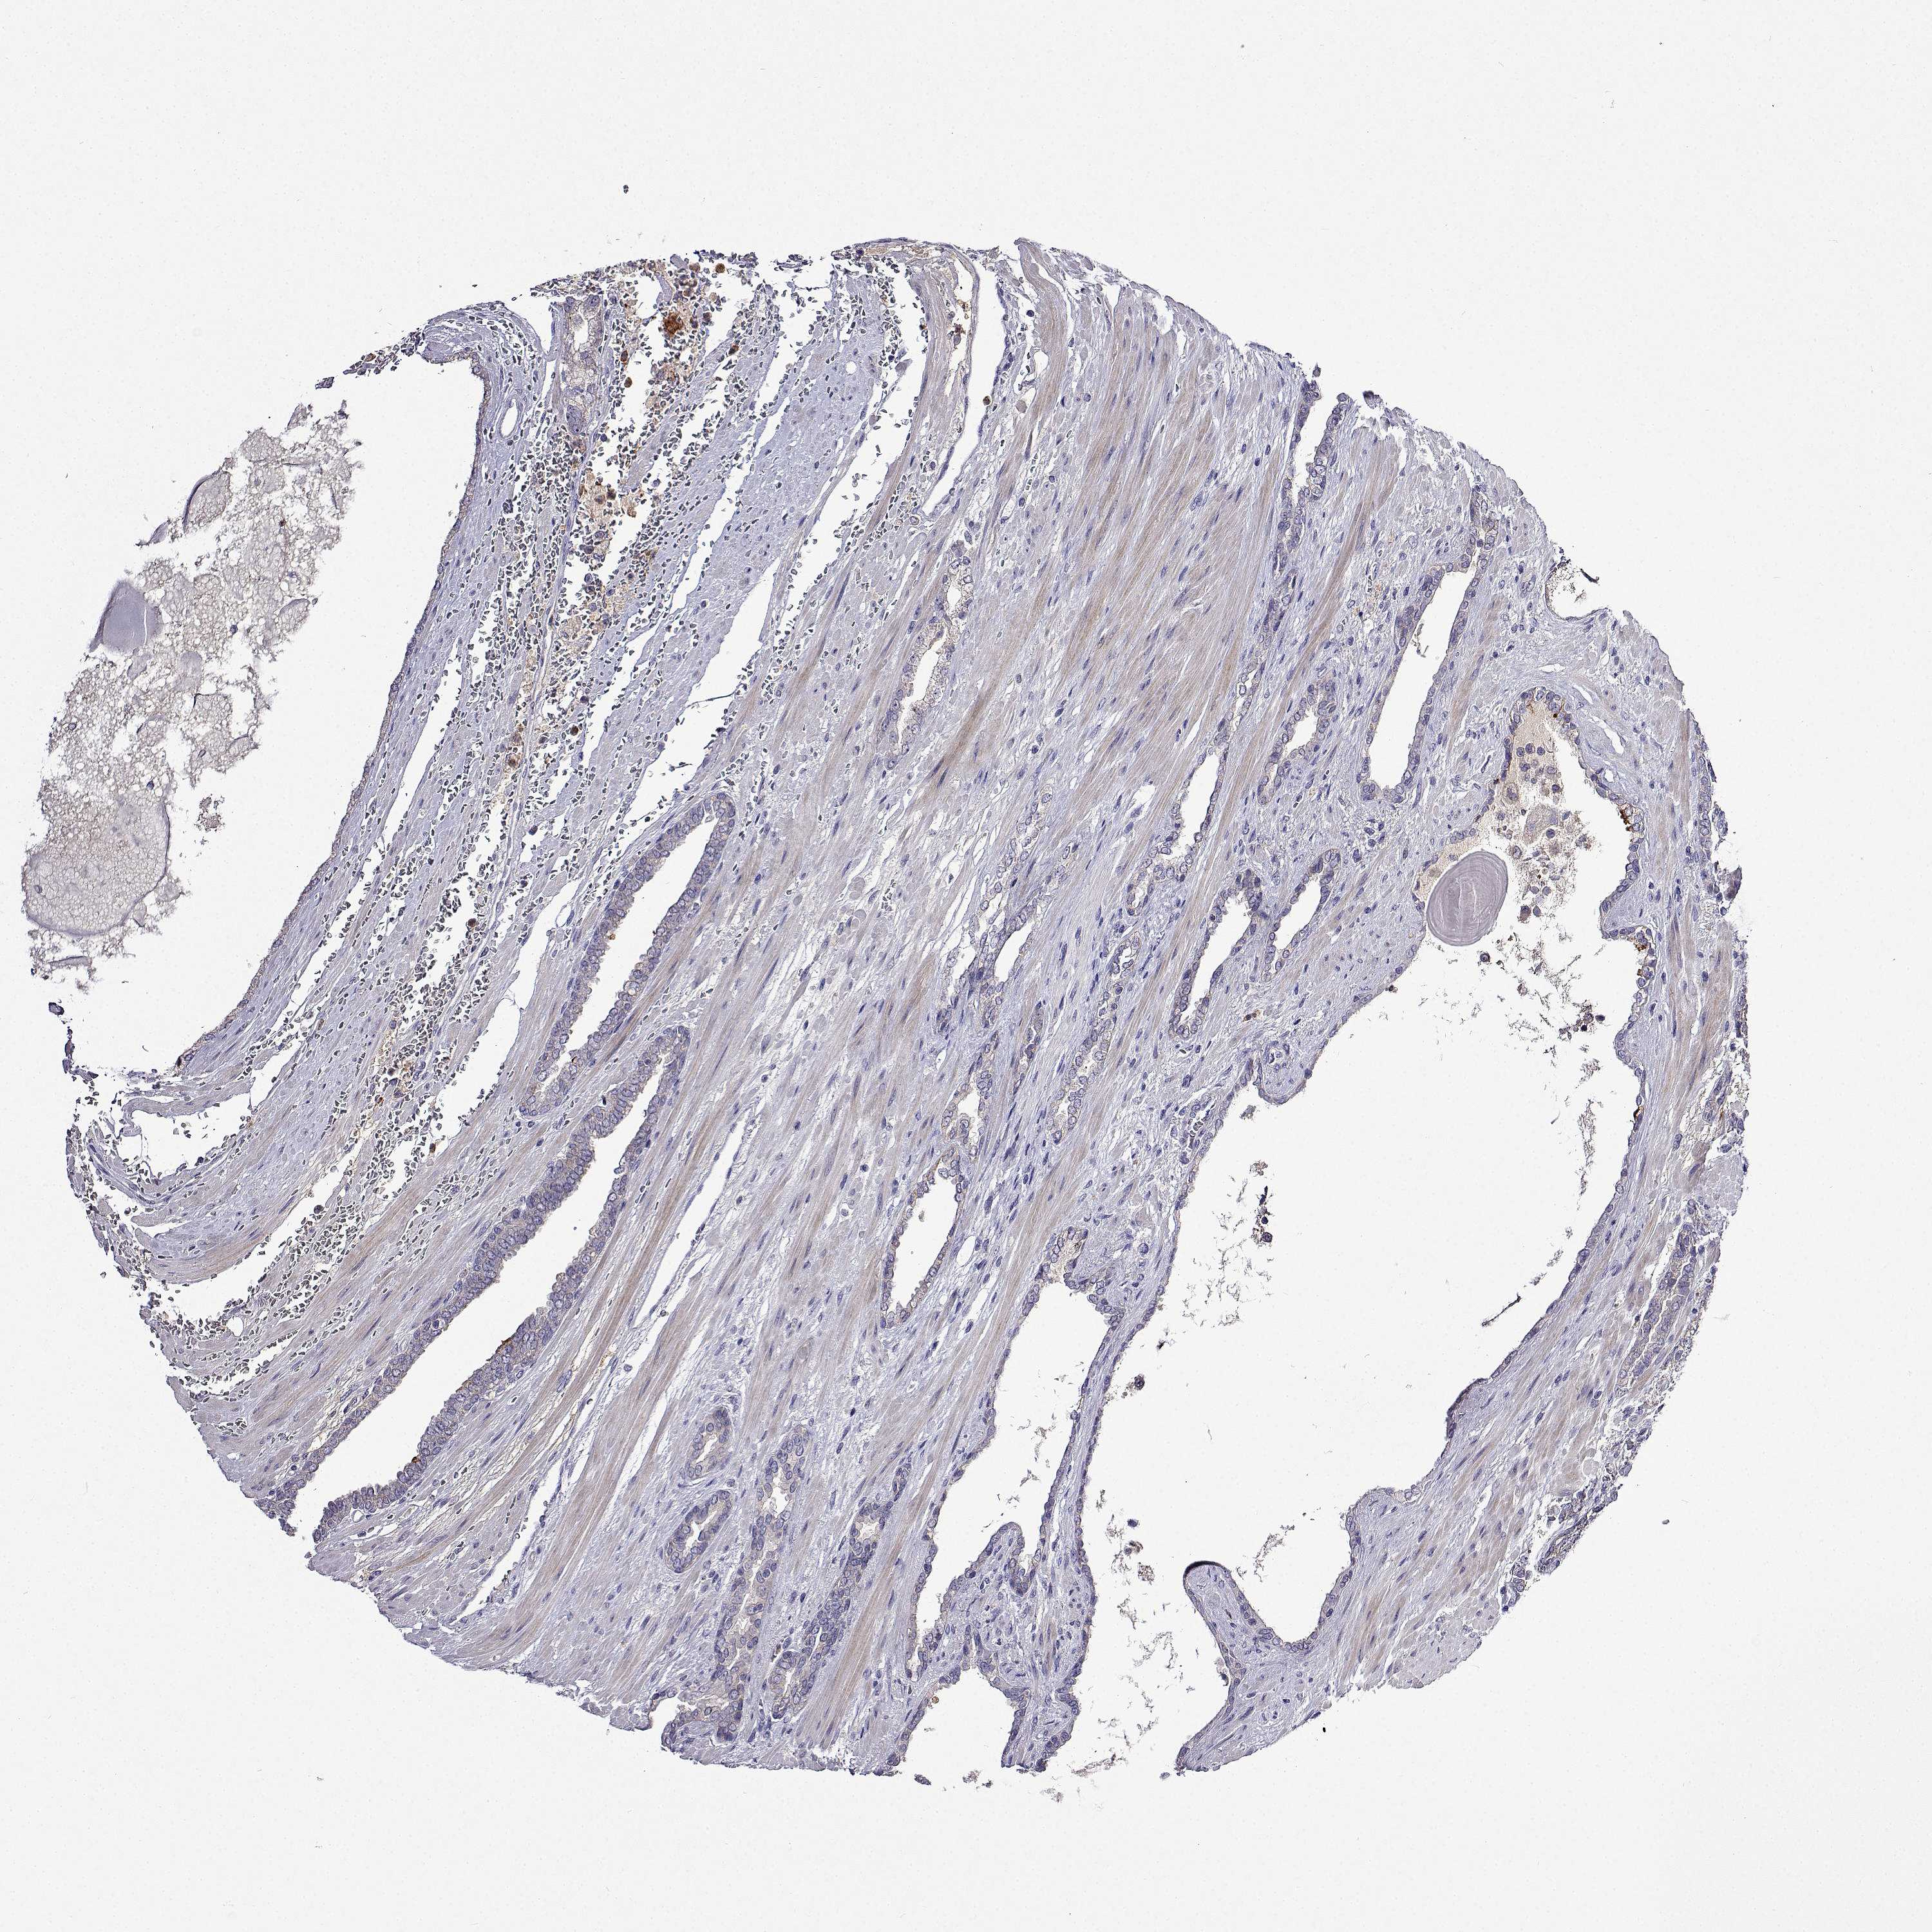

PROSTATE CANCER - Protein expressioni

A mouse-over function shows sample information and annotation data. Click on an image to view it in a full screen mode. Samples can be filtered based on level of antibody staining by selecting one or several of the following categories: high, medium, low and not detected. The assay and annotation is described here.

Antibody stainingi

Antibody staining in the annotated cell types in the current human tissue is reported as not detected, low, medium, or high, based on conventional immunohistochemistry profiling in selected tissues. This score is based on the combination of the staining intensity and fraction of stained cells.

Each image is clickable and will lead to virtual microscopy that enables deeper exploration of all samples and also displays staining intensity scores, fraction scores and subcellular localization as well as patient and tissue information for each sample.

Antibody HPA041487

Antibody HPA063633

Antibody CAB018755

Staining

High

Medium

Low

Not detected

Intensity

Strong

Moderate

Weak

Negative

Quantity

>75%

75%-25%

<25%

None

Location

Nuclear

Cytoplasmic/membranous

Cytoplasmic/membranous,nuclear

Adenocarcinoma, NOS

Adenocarcinoma, High grade

Adenocarcinoma, Low grade